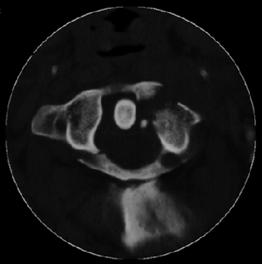

Fractura

Jefferson

Fractura Jefferson Fragmente

osoase la stanga apofizei odontoide

Fractura Jefferson Fractura spanzuratului

Aspect CT